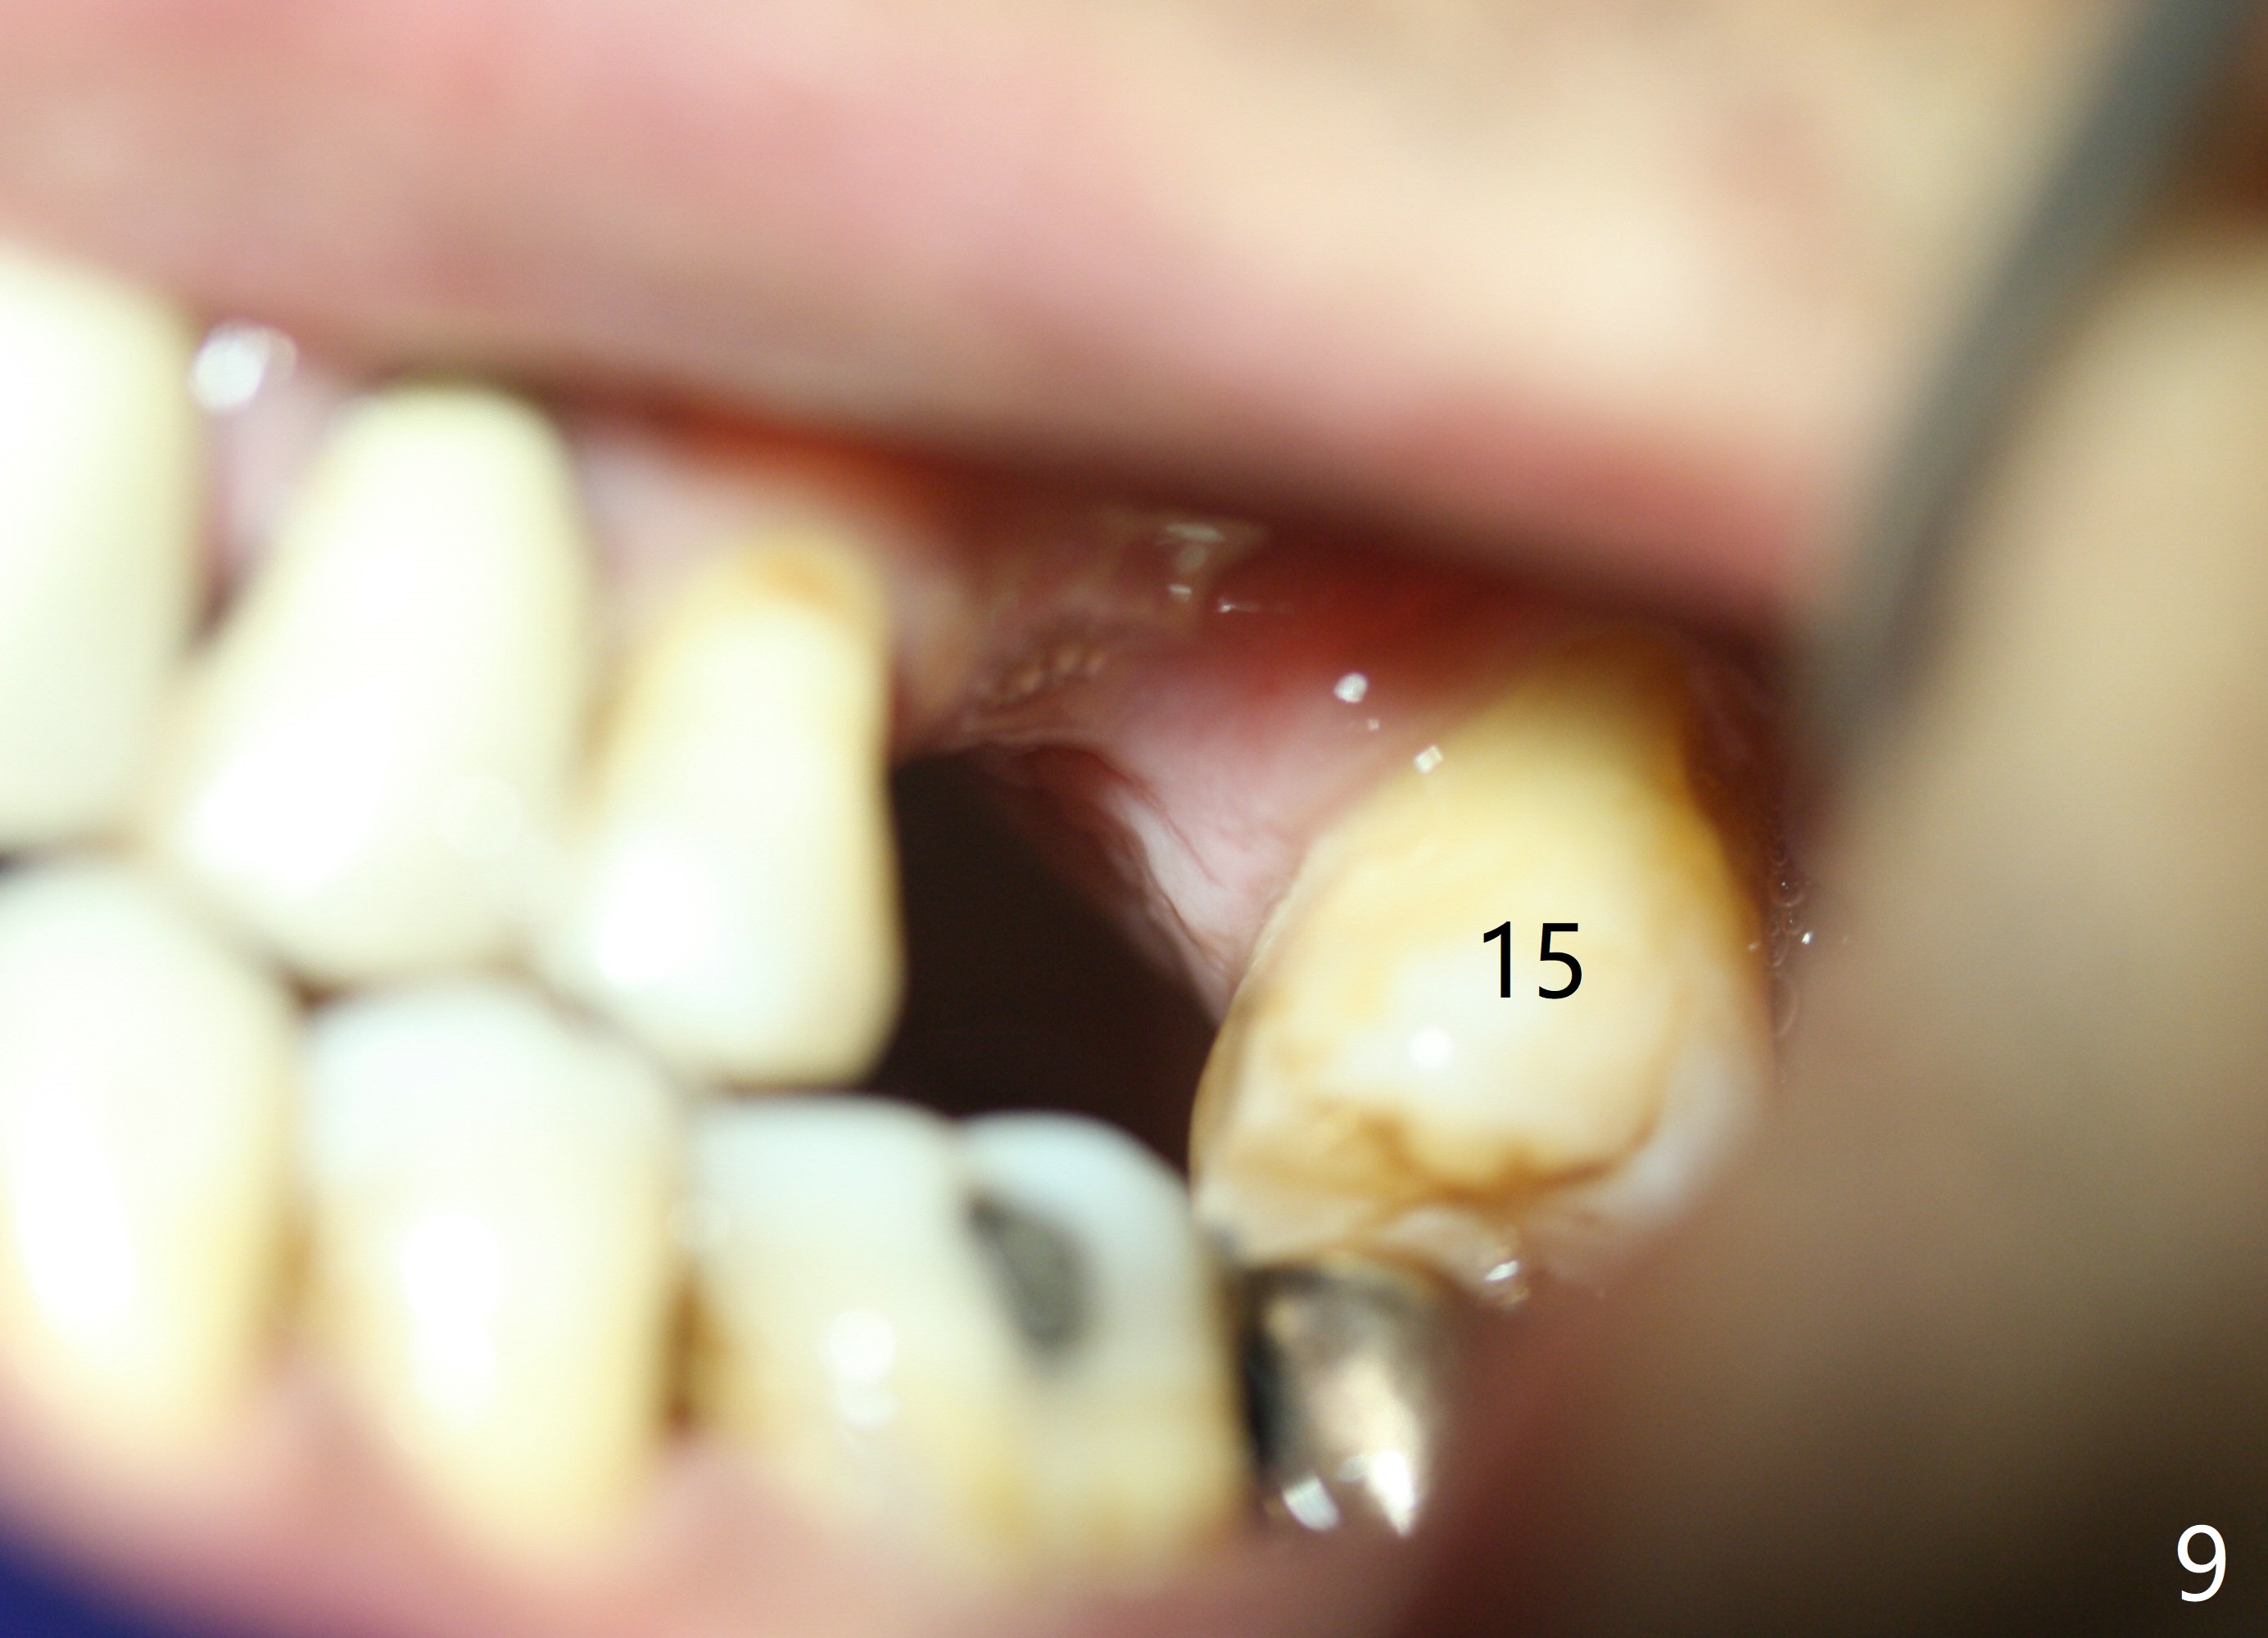

When the tooth #14 is extracted, the buccal plate is lost, while the apex of the palatal socket is perforated. The palatal slope of the septum appears to be a suitable site for osteotomy, but the depth seems to be 2 mm. After sequential osteotomy until 5.3 mm with drills, a 5.9 mm SM tap obtains stability (Fig.2). A 5.9x8 mmm implant is placed with barely sufficient stability after 1 piece of PRF membrane and VeraGraft (Fig.2-4). The implant rotates and dislodges when an abutment is being placed. Neither do 6-8x17 mm Tatum taps achieve primary stability. Socket preservation is performed, followed by periodontal dressing (Fig.5). Primary stability might have been obtained if a smaller IBS implant with fins were placed in the palatal socket. The periodontal dressing has dislodged 1 week postop; the socket appears healing (Fig.6,7). Bone graft seems to be minimal or bone density of the graft is low (Fig.8). The socket heals with a wide ridge 2 months post socket preservation, but the tooth #15 seems to be buccal (Fig.9) and mesial (Fig.10) shift. After use of Magic Split and Expanders (until 3.8 mm for 13 mm), try 5 mm dummy implant (Fig.11). If 6 mm one fails to achieve stability substantially, switch to 7 mm Tatum tapered tap provided there is enough mesiodistal space (use 8 mm implant positioner to gauze the space beforehand (preop)). Consider using Vanilla (not Vera) Graft to fill in the gap between implant and osteotomy. When primary stability is obtained, place a nonfunctional provisional to prevent further shifting (Fig.11 white outline). After osteointegration, use the provisional (reline and separator) to distalize the tooth #15.